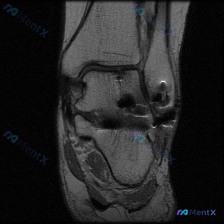

给大家分享一份最近遇到的踝关节MRI读片病例,初始问题指向软骨异常,整理一下完整的分析思路,一起讨论。 一、病例影像基本信息 这是一份踝关节矢状位T2加权MRI图像,图像质量好,信噪比高,解剖结构清晰,涵盖了胫骨远端、距骨、跟骨、足舟骨、骰骨及部分跖骨基底部,胫距关节、距下关节、窦跗管、跟腱等关键结...

看到这个踝关节MRI的读片讨论,整理了完整的影像信息和分析思路,分享给大家。 一、影像基本信息 这是一张踝关节MRI矢状位T2加权图像,T2序列对液体和软组织水肿显示敏感,以下是具体异常发现: 1. 距下关节及跗骨窦区域:距骨下方、跟骨上方的关节间隙及周围软组织可见弥漫性高信号,提示明显积液或炎性水...

刚看到一份踝关节MRI病例,问题是询问影像上观察到的软骨异常相关发现,整理一下资料和分析思路分享给大家。 病例影像基础信息 这是放射影像-踝关节MRI-T2序列-矢状位,系统评估整体结构如下: 1. 骨与关节:胫距关节间隙正常,关节面轮廓可,距骨穹窿皮质连续,未见明确骨折线或弥漫骨髓水肿;距下关节、...

最近碰到一个很有启发的病例,临床问题是问这张踝关节MRI-T1矢状位影像的观察结果是不是软骨异常,整理一下完整分析思路给大家。 一、影像基本信息 本次仅提供踝关节MRI-T1序列-矢状位单张图像,先把客观阅片结果整理出来: 1. 骨骼结构:胫骨远端、距骨、跟骨、足舟骨及部分楔骨显示清晰,骨皮质连续,...

看到这份踝关节MRI的读片申请,核心问题是排查软骨异常,整理了完整的读片和分析思路分享给大家。 一、影像基本信息 这是一张踝关节MRI轴位T2加权图像,扫描层面为踝关节水平,展示胫骨远端后方、距骨及后踝周围软组织结构: 1. 骨结构:胫骨后缘、距骨体后部轮廓清晰,骨皮质低信号、骨髓中等信号,未见明显...